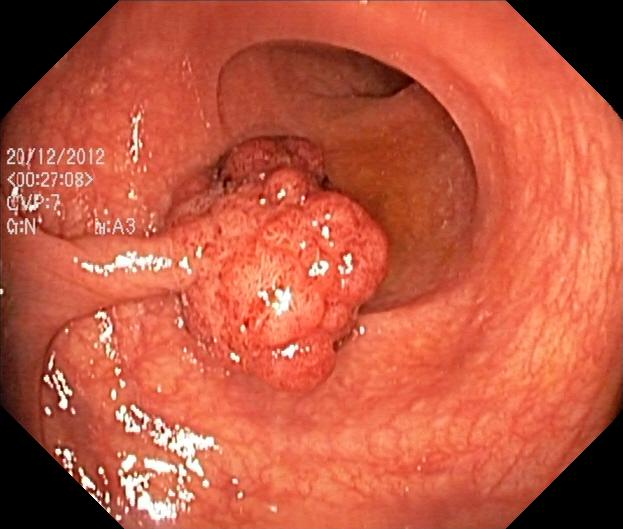

The Kvasir V1 is a datatset of GI-tract images annotated by the medical experts [22]. The dataset consists of 4000 labeled RGB images varying image size from 720×576720\times 576 to 1,920×1,0721,920\times 1,072 pixels. There are 8 classes of the images and each class consists of 500 labeled images. The classes of the images are anatomical landmarks including Z-line, pylorus and cecum, the pathological findings include esophagitis, polyps and ulcerative colitis and removal of polyps including the dyed and lifted polyp and the dyed resection margins.

Hyper Kvasir is a dataset of GI-tract images annotated by various medical domain experts [25]. The dataset consists of 110,800 GPEG images of the GI-Tract abnormalities varying sizes. The image dataset was divided into 10,662 labeled images (training) of 23 classes, 99,417 unlabeled images and 721 images for the test set. The image sizes are varying from 352×332352\times 332 to 1079×19201079\times 1920 with 3 channels. Some of the images from EndoTech 2020 are shown in the Fig. 4. The dataset is highly class imbalance with the minimum 6 images in class hemorrhoids and the maximum of 1148 images in class bbps-2-3. The classes are of five categories including anatomical landmarks, pathological and normal findings and endoscopic procedures.

Figure 4: Some images from Hyper Kvasir Dataset [25]